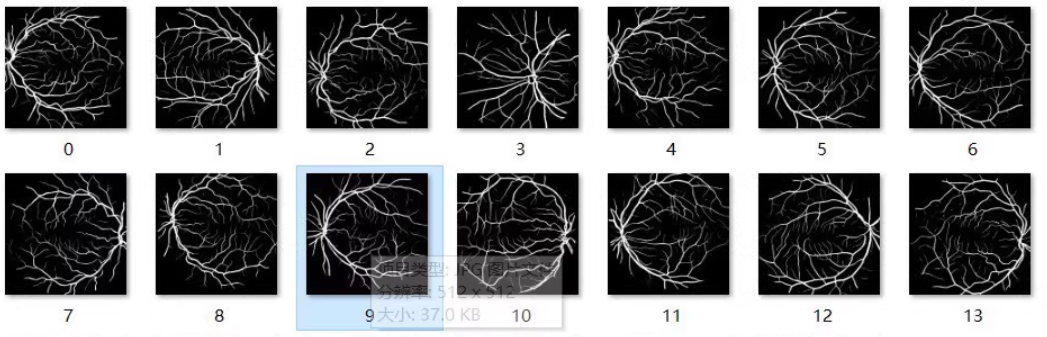

收集和标注眼底血管图像数据集,用于训练UNet模型进行图像分割。常用的公开数据集有DRIVE、STARE等。

数据预处理

对数据进行预处理,包括裁剪、缩放、归一化等操作,以便于模型训练。